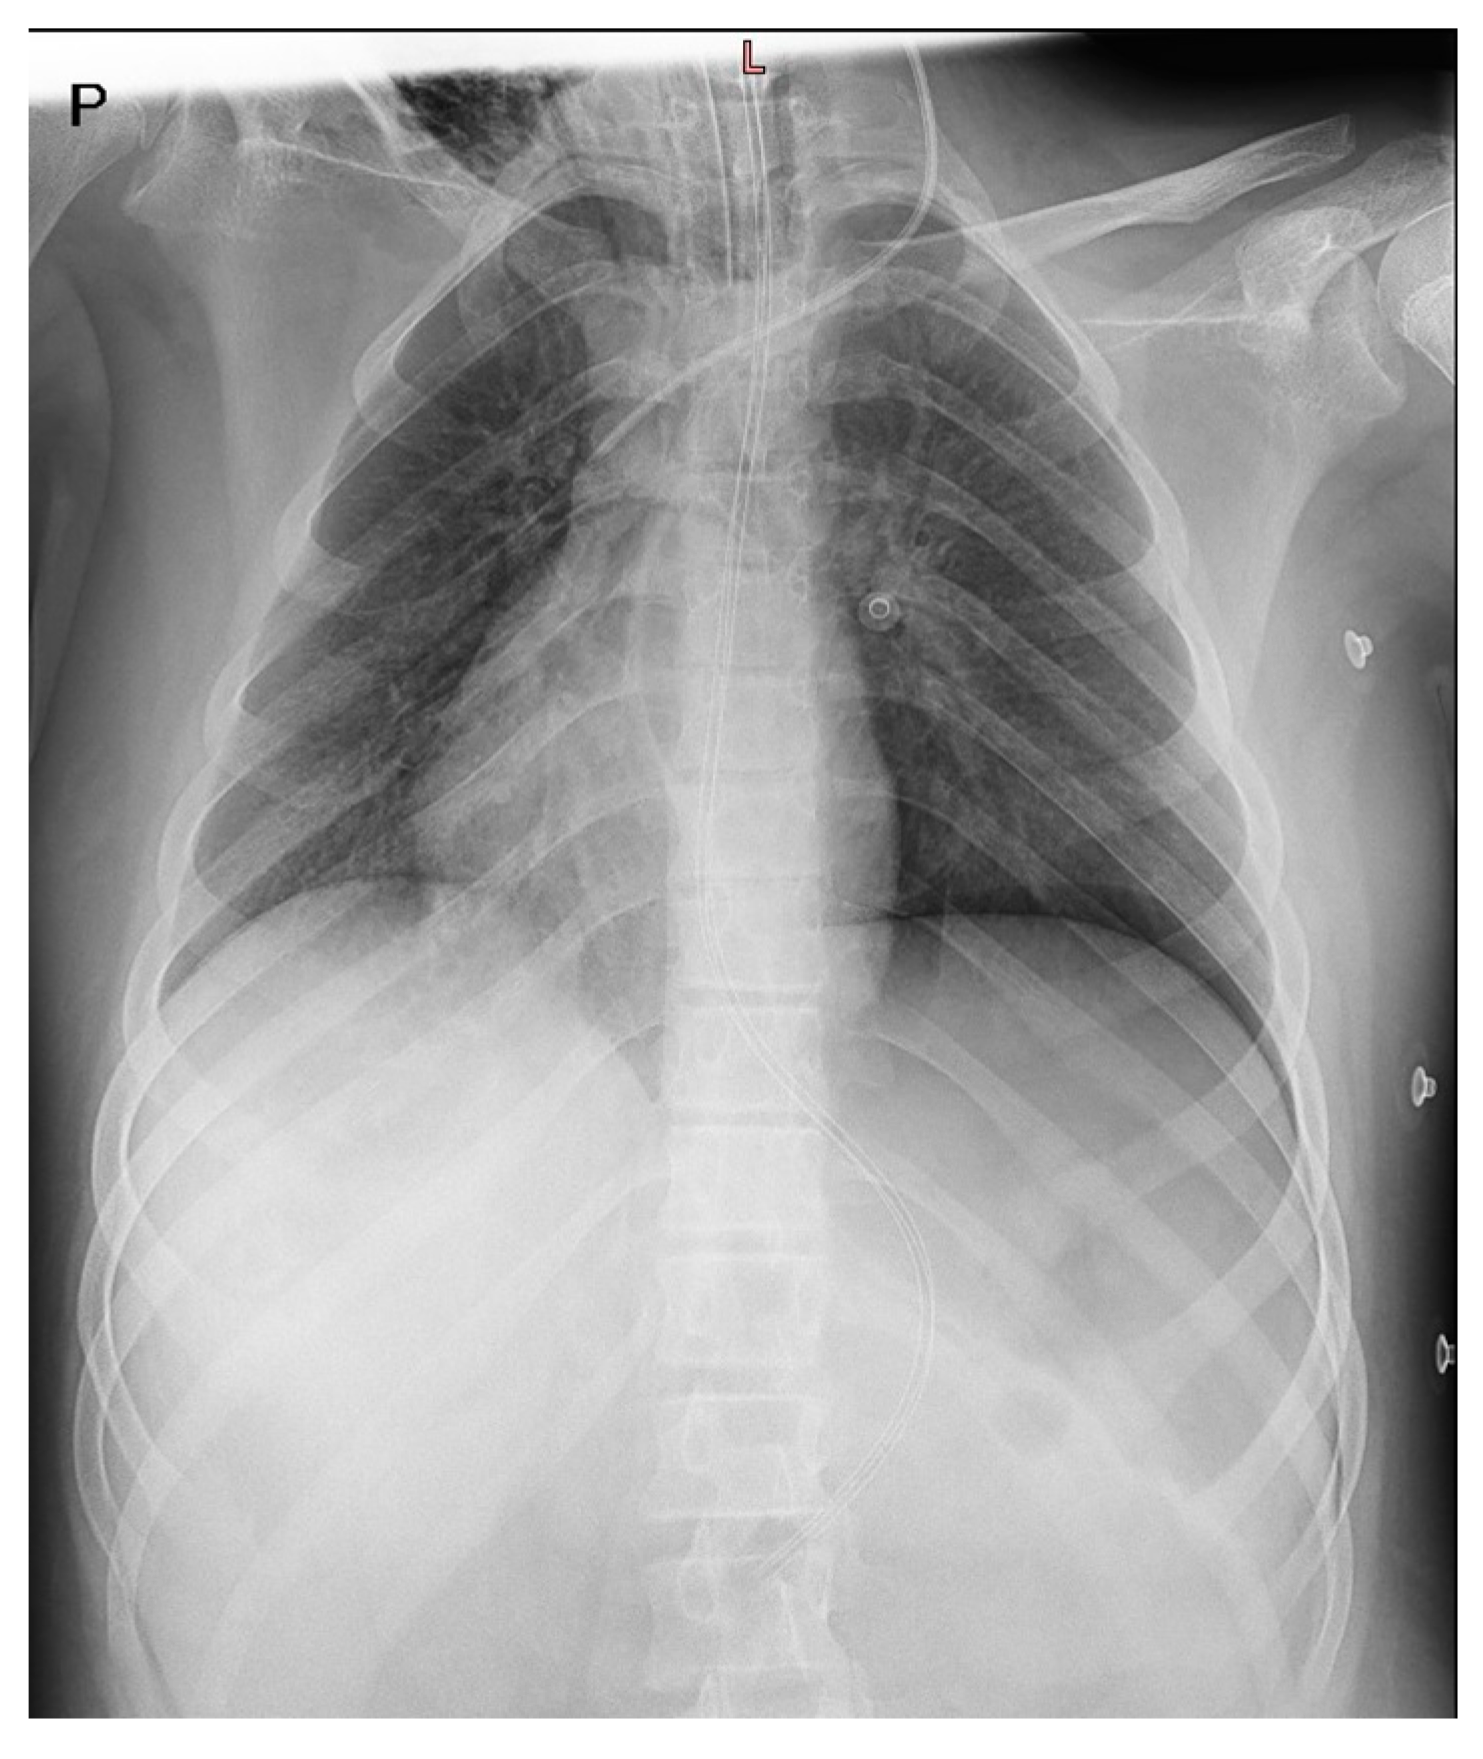

3. Case Report